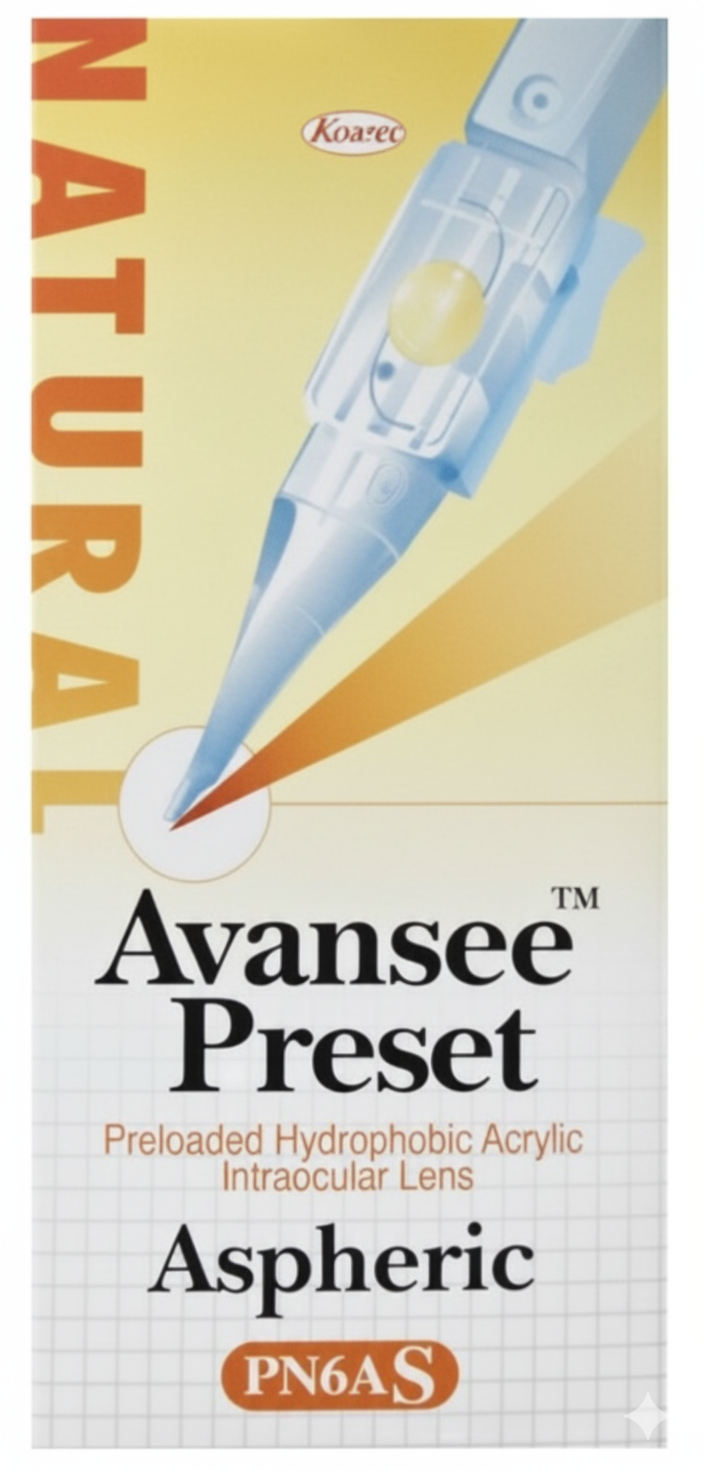

The Kowa AvanseePreset PN6AS is a 3-piece aspheric intraocular lens (IOL) developed by Kowa for implantation following cataract surgery. It belongs to the AvanseePreset family and combines superior optical performance, simplified handling via a preloaded injector, and stable long-term visual results. The ‘A’ in PN6AS represents its aspheric optical design for enhanced image quality.

| Parameter | Details |

| Material | Hydrophobic soft acrylic |

| Refractive Index | 1.519 |

| Overall Diameter | 13.00 mm |

| Optic Diameter | 6.00 mm |

| Optical Design | Biconvex, aspheric (aberration-neutral) |

| Haptics | Modified C-loop, 5° haptic angulation |

| Filtration | UV + Blue light filtering (yellow version) |

| Incision Size | Compatible with 2.4 mm incision using preloaded injector |

| Power Range | +6.0 D to +26.0 D (in 0.5 D increments) |